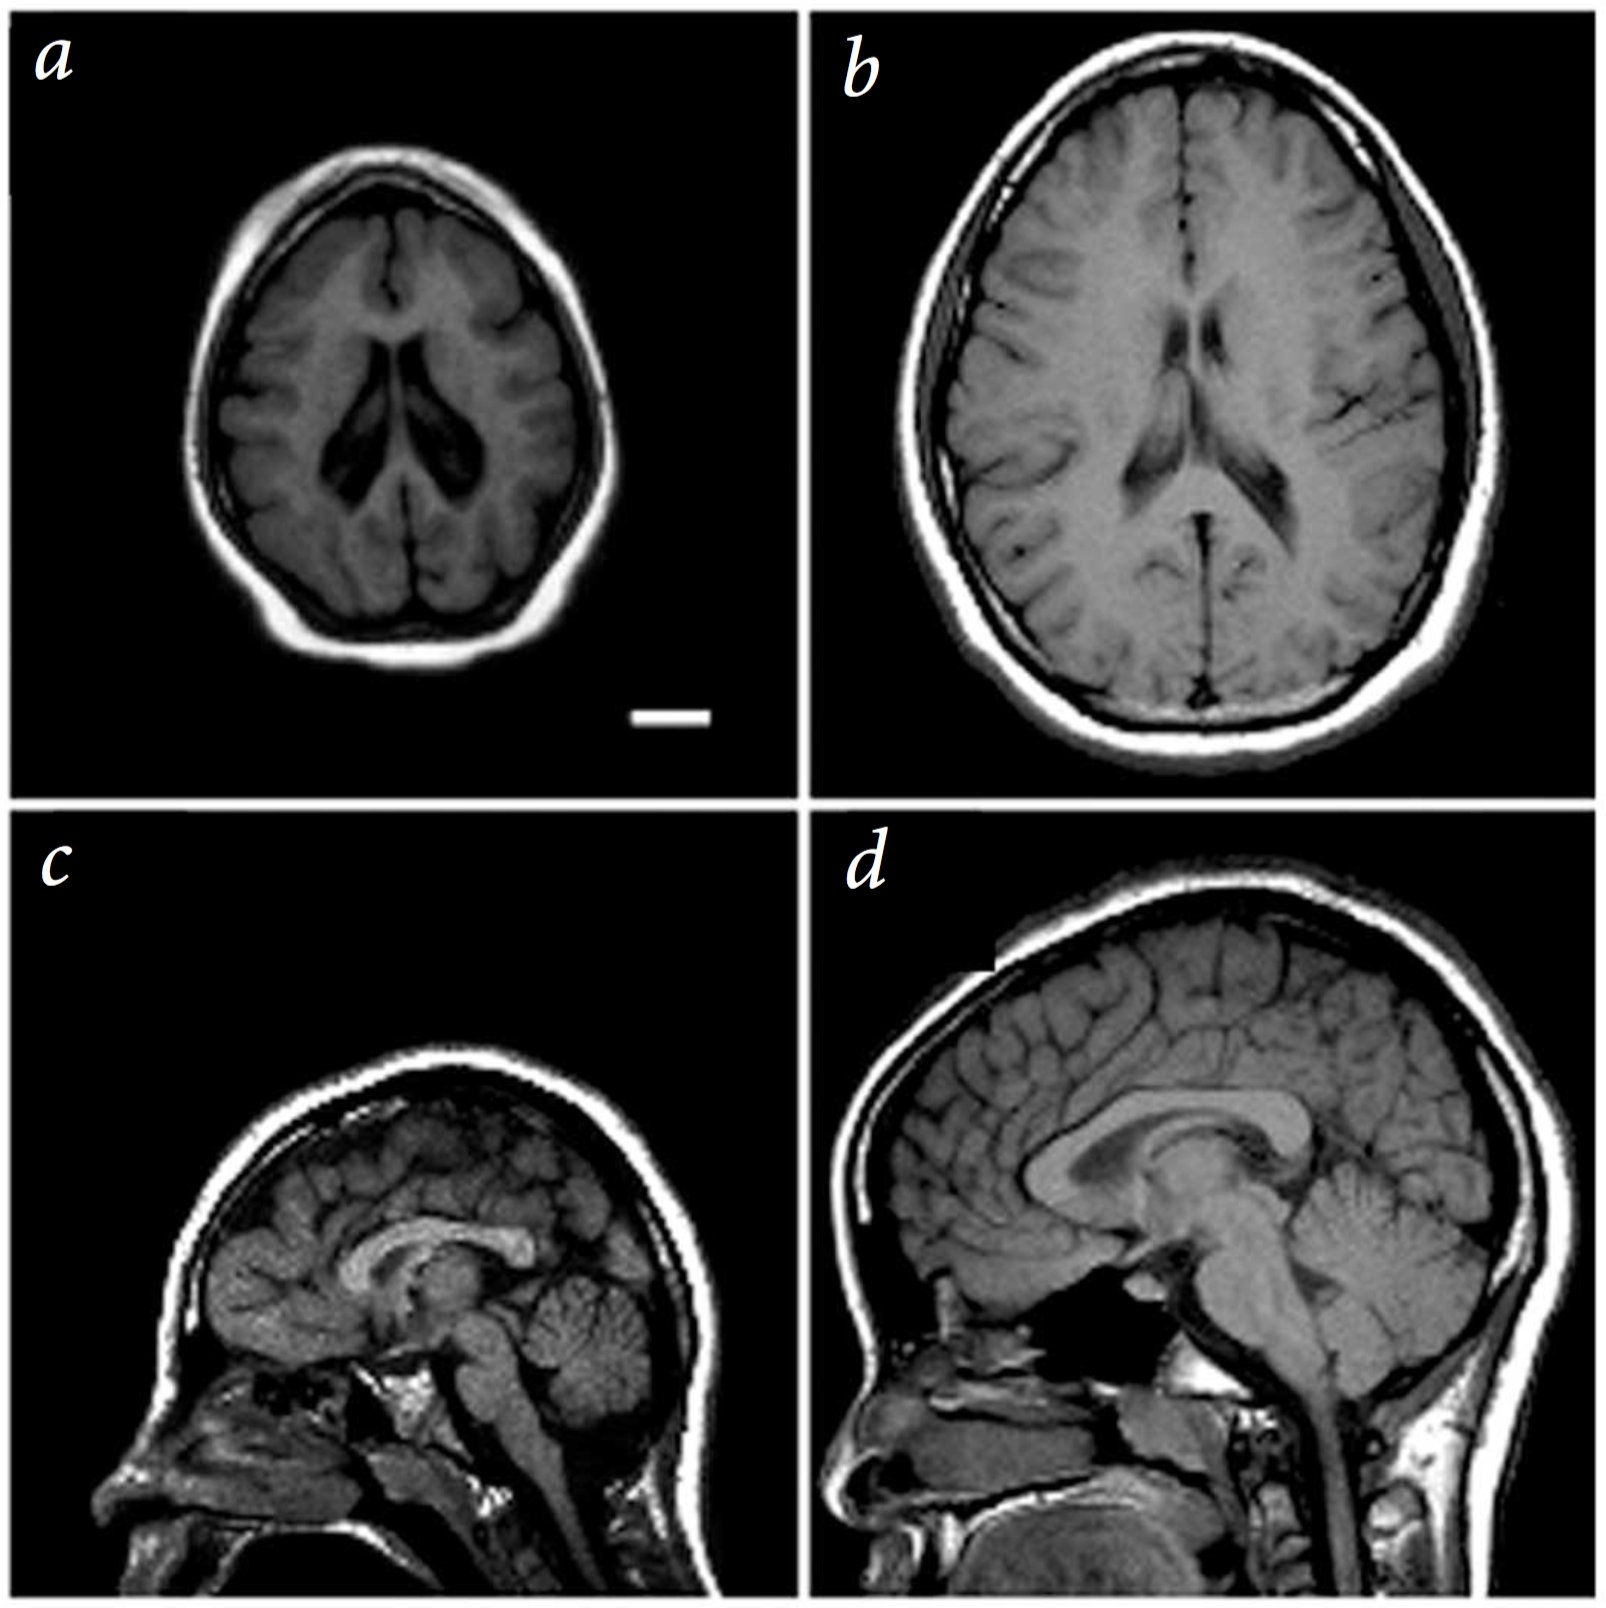

A single mutation can lead to dramatic brain size defects

Mutation in a spindle pole gene call ASPM1 (altered mitosis during brain development)

Bond:2002, see also Neuroscience 5e Fig. 1.1

For example, shown here is a person with a mutation in ASPM1 a protein used to make spindle poles for mitotic stem cells during embryonic development.

But most single gene mutations do not cause such drastic effects, with a more subtle and complex set of genetic and environmental risk factors causing neurological disease, similar to and probably exceeding the complex etiology of cancer.

2cm scale bar. left 13yr old female patient. right 11 yr old control.